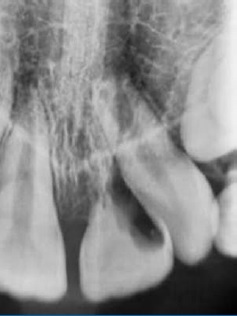

After 3 months of follow-up, the tooth presented a slight metallic sound to the percussion test, and the crown’s color was normal. No signs of ankylosis were observed in the periapical radiograph (Figure 4), and the tooth continued non-responsive to the cold test. In the fourth month of follow-up, the tooth exhibited slight mobility, but no other signs or symptoms were observed. Six months after the trauma, a positive response to the sensibility test was verified. After 9 months, the percussion test suggested ankylosis. The color of the tooth remained stable (Figure 5). A cone beam computed tomography (CBCT) suggested a formation of calcified tissue in the root’s apical third (Figure 6). At the 1-year follow-up, a periapical radiograph showed external root resorption in the cervical third of 21 (Figure 7). The patient did not exhibit fistula, gingivitis, pain, or any change in tooth color. The tooth was in infra-occlusion, and the clinical crown was 7 mm long.

Figure 4 Periapical radiograph three months after the trauma showing no signs of ankylosis or root resorption.